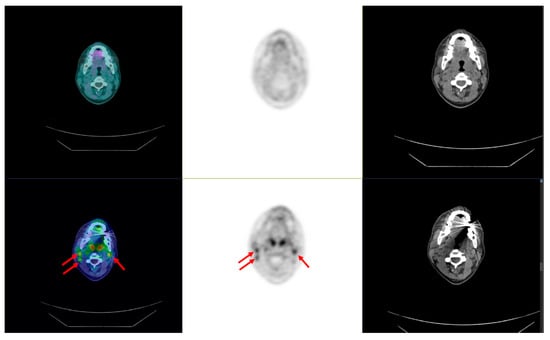

3.4.2. Positron Emission Tomography

- Rosenbaum-Krumme, S.J.; Görges, R.; Bockisch, A.; Binse, I. 18F-FDG PET/CT changes therapy management in high-risk DTC after first radioiodine therapy. Eur. J. Nucl. Med. Mol. Imaging 2012, 39, 1373–1380. [Google Scholar] [CrossRef] [PubMed]

- Giovanella, L.; Ceriani, L.; De Palma, D.; Suriano, S.; Castellani, M.; Verburg, F.A. Relationship between serum thyroglobulin and 18FDG-PET/CT in 131I-negative differentiated thyroid carcinomas. Head Neck 2012, 34, 626–631. [Google Scholar] [CrossRef]

- Giovanella, L.; Trimboli, P.; Verburg, F.A.; Treglia, G.; Piccardo, A.; Foppiani, L.; Ceriani, L. Thyroglobulin levels and thyroglobulin doubling time independently predict a positive 18F-FDG PET/CT scan in patients with biochemical recurrence of differentiated thyroid carcinoma. Eur. J. Nucl. Med. Mol. Imaging 2013, 40, 874–880. [Google Scholar] [CrossRef] [PubMed]